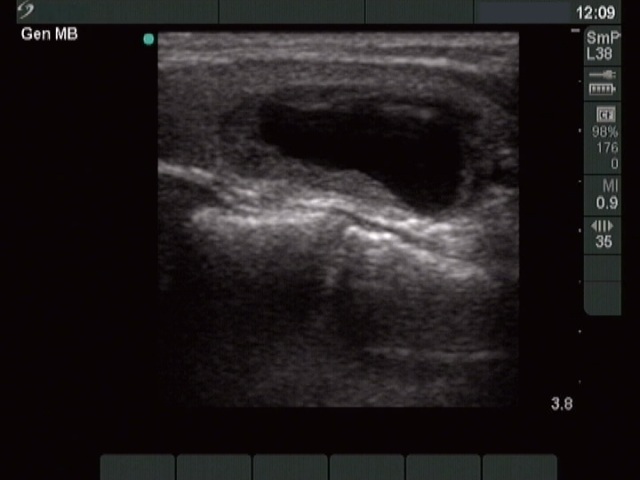

Ethanol sclerotherapy: thyroid cysts - Case 11

First session of the therapy (ultrasonographic picture 2)

Left lobe, longitudinal scan.